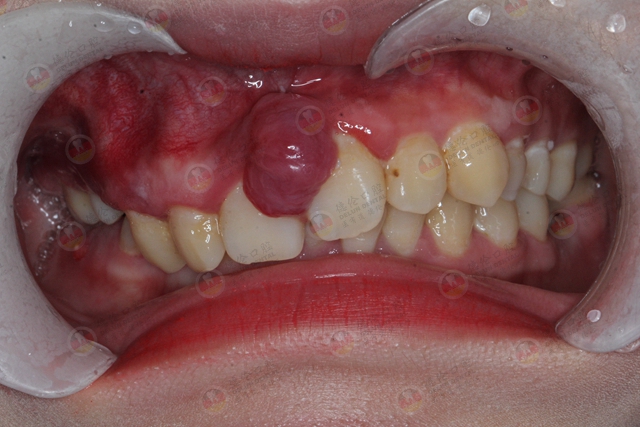

#03、牙周脓肿

牙周脓肿是牙周炎晚期,出现较深的牙周袋之后一种较为常见的症状,是位于牙周袋壁或深部牙周组织的化脓性炎症。

脓液未能及时排除,就会引起局部肿胀,在牙龈形成椭圆形或半球状的红肿突起。

牙周脓肿的高发人群为牙周炎中、晚期,牙槽骨吸收,形成较深牙周袋者,食物残渣与细菌容易在牙周袋内聚集,久而久之细菌大量繁殖产生毒素,就会形成一个脓包。